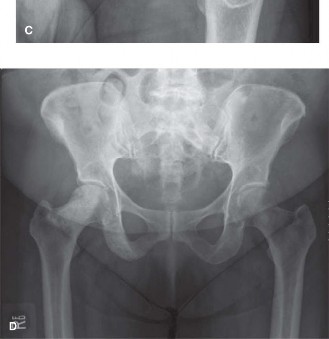

Initial plain radiographs of the left hip were obtained upon presentation. The anteroposterior (AP) and lateral views of the left hip demonstrated a comminuted, subtrochanteric fracture of the left femur. The fracture pattern involved significant cortical destruction and a large lytic lesion extending proximally into the intertrochanteric region and distally into the subtrochanteric area. The margins of the lytic lesion appeared ill-defined in several areas, raising strong suspicion for a neoplastic process. There was no evidence of periosteal reaction or overt sclerotic changes commonly associated with benign lesions or healing fractures.

This uncoupling results in aggressive osteolysis, presenting radiographically as punched-out lytic lesions, diffuse osteopenia, and ultimately, pathological fractures. The subtrochanteric region of the femur is particularly susceptible to these catastrophic failures due to its unique biomechanical environment, where immense physiological loads are concentrated across areas of focal cortical destruction.